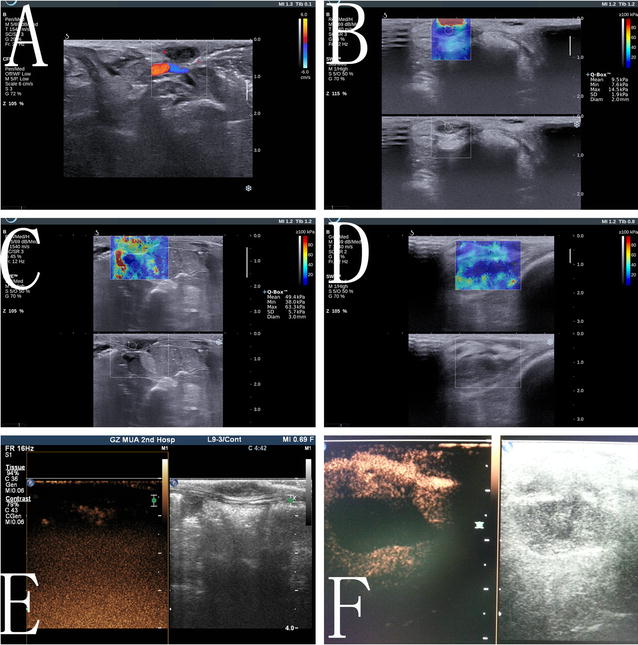

摘要:目的探讨不可逆电穿孔(IRE)对乳腺组织和乳腺癌动物模型的安全性、可行性和皮肤效应。方法:在这项研究中使用了八头猪。用不同皮肤-电极距离的猪的左乳房进行不可逆电穿孔,右乳房作对照。电极被放置在离皮肤1 - 8毫米的地方,电极间距为1.5 - 2厘米。在特定时间点进行影像学和病理学检查评估。密切观察动物生命体征、皮肤损伤、乳腺组织变化和消融疗效。8只有VX2乳腺癌植入或没有的模型兔用以进一步评估乳腺癌治疗后薄皮的损伤和修复。超声造影与超声弹性成像观察消融的疗效和安全性。结果:在不可逆电穿孔过程中,猪乳房皮肤的颜色发生了可逆的变化。皮肤-电极距离为3毫米时,乳房皮肤颜色明显改变,在中心区域变成白色,周围区域为紫色。不可逆电穿孔几天后,检测出小的化脓性皮肤损伤。当皮肤-电极距离为5 - 8毫米时,乳房皮肤在不可逆电穿孔过程时变红。然而,用大体病理学和苏木精-伊红染色评估发现皮肤结构是正常的。当皮肤-电极间距为1 mm,兔乳房皮肤出现萎缩。当皮肤-电极间距为≥5 mm,无论有无乳腺癌细胞植入的家兔模型均无皮肤损伤。不可逆电穿孔后,已确定靶乳腺组织或癌完全消融,靶组织和最外层表皮细胞均有凋亡。在幸存的动物乳房中,发现正常皮肤和完整毛发的乳房再生。此外,超声或HE染色均未发现大面积纤维化或肿块形成。结论:在不可逆电穿孔过程中,当皮肤-电极距离≥5毫米时皮肤结构保存完好。乳腺再生无肿块形成或明显纤维化。关键词:不可逆电穿孔 乳腺 成像 病理 细胞凋亡 皮肤背景:近年来,乳腺癌保乳治疗的使用已得到临床证据的支持,影像引导下的消融技术,如射频消融、高强度聚焦超声,已成为乳腺肿瘤的治疗有用的方式。在乳腺癌切除术中,如果病灶太大或表面较浅,乳房皮肤可能受损,不完全消融可能发生以防止损伤。此外,许多亚洲妇女乳房体积相对较小,因此在这一人群中,热消融时皮肤损伤的风险增加。放疗后保乳纤维化(即乳腺和皮肤纤维化)是放疗后常见的晚期毒性。约45%的患者经历了辐射引起的纤维化相关疼痛,在切除有放射性纤维化的组织后可能发生更严重的纤维化。这是影响乳腺癌放疗后生存质量和美容效果的主要因素。乳腺癌切除后,如果皮肤没有受损,正常乳腺组织再生,无肿块形成或残留肿瘤,则上述问题将得到解决。不可逆电穿孔技术的应用使这一目标成为可能,因为在烧伤后皮肤细胞凋亡可能是有选择性的。但是还没有在大的动物模型中研究使用乳腺癌根治术的报告。以前的研究主要报道了IRE的疗效,但我们集中在皮肤损伤,纤维斑块的形成和消融后乳房的重吸收。在这项研究中,我们对两种动物乳腺癌模型用接近皮肤表面的电极(1 - 8毫米)进行了治疗。评估了它的安全性和可行性,特别是它对皮肤的潜在损伤及导致乳房纤维化的形成。方法:用五指山猪进行正常乳房的射频消融实验研究。用新西兰大白兔进行乳腺癌和乳腺癌的射频消融研究。猪的胸部比较大,皮肤厚,便于在进行皮肤手术时准确测定电极与皮肤的距离。局部乳腺癌的皮肤可能不同于典型的健康皮肤,皮肤变薄可能是由于营养不良、皮肤侵犯和局部肿瘤张力引起的。因此,不可逆电穿孔热损伤皮肤的风险会增加。由于兔皮肤薄,我们用新西兰大白兔研究皮肤损伤。建立了兔VX2肿瘤模型,以检验乳腺癌根治术的安全性。在不可逆电穿孔治疗前和治疗后,通过大体病理和组织病理学对所有乳腺动物的乳房、乳头、肌肉、乳腺导管和乳腺、乳房肿块形成、消融区纤维化和乳房再生进行了评估。不可逆电穿孔:所有的动物在手术前禁食12小时。备皮,消毒和覆盖洞巾。手术开始前肌注舒泰(4.4 mg/kg),静脉注射3%戊巴比妥钠(1ml/ kg)维持全身麻醉。所有的动物在术前皮下注射0.01毫克/公斤丁丙诺啡镇痛,然后每12小时一次连续72小时。在IRE过程中,每只动物接受琥珀酰胆碱(2 mg/kg)。在IRE前10min,静脉注射泮库溴铵(0.15 mg/kg)减少肌肉收缩。计算机断层扫描(CT)和超声引导下,确定皮肤和电极之间的精确间距。一位经验丰富的技术专家进行CT和磁共振成像(MRI)扫描。采用实时超声监测技术将乳腺电极植入乳房的正常位置。研究组有超过5年的介入放射学经验。乳头位于两个电极之间,在研究中大部分乳房位于消融区。平行电极和合适的位置也被CT扫描所证实。肌肉完全放松后,我们开始使用心电图(ECG)同步模式进行射频消融。IRE后,回顾了电压和电流图以及超声造影和CT图像来评估消融效果。如果没有完成靶区的完全消融,则重复治疗。猪乳房的IRE消融:健康成年五指山猪8头,体重16~18公斤,分为IRE组(6头猪)和假处理组(2头猪)。三只猪的左乳房被消融或加工。右乳房被用作对照,任何猪的都不接受治疗。假手术组在不做消融的情况下,将电极插入左乳房。在IRE组,进行左侧乳房的IRE消融。在IRE组,一头猪有三个乳房,电极和皮肤之间的距离为3毫米,剩下的五只猪电极和皮肤之间的距离为5到8毫米。电极和皮肤之间的距离被定义为电极与皮肤表面暴露部分之间的最短距离。假手术组在不做消融的同时,将电极插入乳房的预定位置。围手术期进行CT和MRI,做活检或切除乳房作病理检查。家兔乳房的IRE消融:为了确定是否会破坏薄皮肤,在新西兰大白兔身上放置了接近乳房皮肤(1或3毫米)的电极。电极保持平行于皮肤平面,四个消融区的距离为1毫米,另外四个消融区为3毫米。总共对四只兔子进行了八次IRE试验。IRE之后的1, 3, 7天和14天,检查肿块形成、纤维化和皮肤变化。乳腺癌模型的IRE: 将新鲜的VX2肿瘤分成1 - 2毫米直径的组织块,没有坏死或液化碎片。我们在四只兔子的乳房皮下植入一个新的肿瘤。每只兔子产生两个乳腺癌模型。皮肤-电极距离小于8毫米。1周后,所有8个乳腺肿瘤直径增加到1到1.5厘米,用超声评估肿瘤大小。在IRE开始前、开始后1天和7天用彩色多普勒超声、超声弹性成像及超声造影。我们于第3天切除了4只兔子的四个乳腺肿瘤,进行病理检查;在实验后期的时间点,没有超声波检查。剩下的4个乳腺肿瘤定期评估至少1个月。用超声造影评估是否完全消融,并应用超声弹性成像技术检测IRE后组织刚度的变化,作为评估完全消融的一个潜在的方法。弹性成像探头频率为4-15 MHz。选择合适的切片后,切换到实时剪切波弹性成像模型,并在消融区放置一个弹性成像取样框架。在3~5 s图像稳定后,将90%的图像采样帧填充为彩色,选择直径为3厘米的周期作为测量区域,得到平均弹性值。测量重复三次。尽量避免在表面皮肤留下超声波探头的痕迹。超声造影成像,静脉注射1.2毫升的sulfohexafluoride微泡后,我们开始约2分钟的影像。所使用的超声波频率为3 - 9兆赫。IRE之前和之后进行超声弹性成像及超声造影。HE染色与免疫组织化学:取乳房标本进行HE染色和细胞凋亡试验。IRE后立即及1、3和1周后用TUNEL和caspase-3对凋亡细胞进行检测。TUNEL阳性结果为棕黄色核染色。caspase-3蛋白阳性染色为胞浆棕黄色染色。评估了皮肤、乳腺血管、肌肉、乳腺、导管和基质中的凋亡细胞分布。结果:猪乳房的IRE消融:在皮肤-电极距离为3毫米IRE之后,猪胸部皮肤的颜色开始变为红色,然后变成白色,然后变成紫色,最后恢复到正常的颜色。术后2周,皮肤局部有少量化脓灶。痂形成,4周后,皮肤就恢复正常。其余两个乳房正常。当皮肤-电极距离约为5 - 8毫米时,乳房皮肤变红,消融区的中心区域变成白色,乳头周围有红色。皮肤-电极距离越近,术中皮肤颜色变化越明显和迅速。2小时后皮肤颜色恢复正常,穿刺点变红时可见少量液体。IRE之后,消融的乳房充血,肿胀,坚硬。在3个月内,大多数动物的乳房皮肤都是正常的,有完整的毛发和皮肤。在消融后3个月,消融区无纤维质形成。兔乳腺及乳腺癌的IRE消融: IRE之前,兔的乳房皮肤看起来正常。当皮肤-电极距离为1毫米时,皮肤在IRE后变红。术后第三天出现一个小的化脓性病变。一周后,皮肤表现出黄化、脱落。2周后,皮肤再生,无瘢痕形成。三周后,皮肤上只出现一个小痂,新毛发生长明显,消融区大部分皮肤恢复正常。IRE两个月后,皮肤和肌肉周围的乳腺组织正常。其他三个乳房,皮肤变得干燥和黄色,脱毛发生1周后。术后2周无化脓灶,但新皮肤生长,3周后毛发和皮肤均正常。当皮肤-电极距离为3毫米时,四个消融区的皮肤颜色瞬间变为红色,没有皮肤结构损伤或脱发,家兔乳房内无瘢痕或纤维化形成。建立兔乳腺VX2肿瘤模型后,通过病理评估和超声证实肿瘤的形成。植入后10天肿瘤直径逐渐增加1~2厘米,无液化或坏死。IRE后第一天,乳腺肿瘤变硬变大,第二天肿瘤开始变软萎缩,呈时间依赖性。当皮肤-电极距离为1毫米时,一个乳房的皮肤有脓毒症的迹象,并有疤痕愈合。当皮肤-电极距离约为3毫米时,覆盖肿瘤的乳房皮肤出现化脓,并且在消融区域没有发现血液供应。当皮肤-电极间的距离≥5毫米,没有皮肤溃烂化脓或脱毛的迹象。一个月后,所有的动物都有正常的乳房皮肤。HE染色:IRE之后,消融的乳房变得充血、肿胀和坚硬。围绕着电极束,乳房颜色变成棕黑色。IRE后立即观察在乳房的腺体和导管细胞中发现空泡。IRE后2h到3天,乳腺导管浆液分泌,某些导管细胞脱落,中性粒细胞,嗜酸性粒细胞和浆细胞浸润。未观察到乳腺上皮分层上皮结构的明显损伤。IRE后三天,电极路径附近可见成纤维细胞和胶原形成,也可见横纹肌断裂和溶解。IRE后一周,消融区皮肤皮脂腺和毛发正常。IRE十四天后,在乳房中观察到乳腺再生和恢复正常乳腺组织结构,无导管狭窄、扩张或闭塞。在任何消融区均无大面积纤维化或肿块形成。假手术组和对照组在电极路径上有少量出血,3周后形成胶原纤维,无细胞凋亡或炎性浸润。IRE后两个月,实验猪的消融区出现正常的乳腺组织。皮肤胶原、发根、汗腺或皮脂腺中没有观察到结构异常。3个月内无肿块形成或乳管阻塞。对于正常家兔,当皮肤-电极距离在1~3 mm时,HE染色显示胶原纤维完整,皮肤结构正常。电极周围的通道均匀红染,IRE 2周后乳房内无纤维化或肿块形成。乳腺肿瘤切除后,皮肤内可见炎细胞浸润和少量红细胞浸润。消融后的乳房肿瘤在3周后逐渐消失,没有肿块形成,以前的消融区被正常的乳房组织所取代。细胞凋亡检测:在IRE的3天内,在消融区检测到Caspase-3阳性细胞质染色。猪IRE组,乳腺腺泡细胞、导管上皮细胞、脂肪细胞、间质细胞、血管内皮细胞和血管平滑肌细胞均呈阳性的TUNEL染色。染色阳性细胞数量呈时间依赖性增加,在第三天100%的细胞发生凋亡。假手术组和对照组均未检测到细胞凋亡。在乳腺组织中也检测到乳腺血管内皮细胞和血管平滑肌细胞的凋亡。IRE消融后2小时,表皮鳞状上皮细胞最外层可见少量凋亡细胞,第三天凋亡细胞增多。IRE十四天后,任何乳房都没有发现细胞凋亡。成像:IRE之后,消融的乳房充血、肿胀、增大,通过CT和磁共振成像证实。IRE一周后,CT显示猪胸部轻度充血和水肿。2个月后,切除的乳腺区域的超声表现正常。使用CT对乳腺皮肤和乳腺组织进行完整的分层结构观察,乳腺结构性完整正常,无瘢痕、囊肿或肿块形成。3个月后,每只猪表现出正常的乳房、皮肤和乳头外观。IRE消融后即刻超声评价表明,兔乳腺肿瘤消融区呈低回声无增强。超声弹性成像显示肿瘤弹性值有所提高。IRE七天后,肿瘤仍低回声无增强,采用超声弹性成像弹性值明显下降。结论:研究表明乳腺癌的根治术是可行和安全的。在皮肤-电极距离≥5毫米,乳腺组织和乳腺癌被IRE完全消融后,皮肤的结构保存完好。此外,实验动物的凋亡组织和乳腺再生迅速消失,无大量纤维化或肿块形成。对于乳腺癌的切除,特别是对易感皮肤的浅表肿瘤,IRE是一种潜在的选择。由于人类和动物之间的解剖差异,有必要进一步通过临床试验评估乳腺癌切除后皮肤的变化。